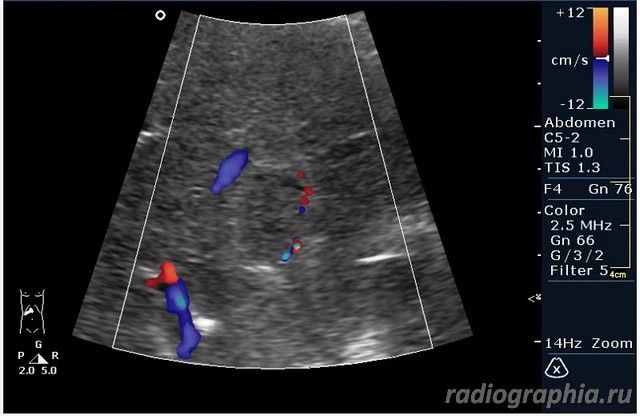

УЗИ печени. Женщина 37 лет. Жалобы на боли в эпигастрии; в печени обнаружено такое образование...

Считаю,что это опухоль,имеет неоднородную структуру,четкий контур,прорастает в сосуд(есть один такой скан) И,вообще,вся поверхность печени НЕСПОКОЙНАЯ,могут быть мелкие МТ.Интересно,что на КТ?

так и хочется назвать это метастазами но уж очень они красивые и доброжелательние по структуре (изоехогенные по отношению к структуре печени) и они больше компресирують чем проростают, склонен к ответу о доброкачественной гиперплазии. так что же на КТ?

гемангиома,рядом питающий сосуд

Мне тоже нравится версия, что это - гемангиома.Нелли писал(а):гемангиома,рядом питающий сосуд

Спсибо,но...вся печень какая-то неоднородная.